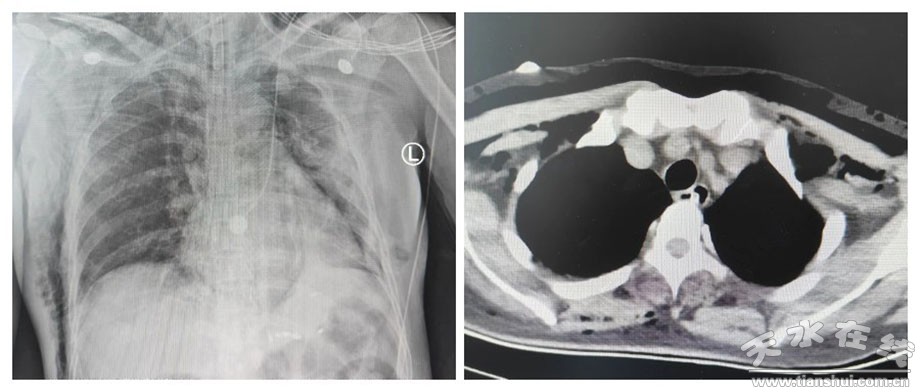

7月4日13:30在市一院內(nèi)鏡中心和麻醉科的協(xié)助下,進(jìn)行全身麻醉+氣管插管,手術(shù)過程中,在蘭大一院姬瑞主任醫(yī)師的指導(dǎo)下,消化內(nèi)科茍金平主任醫(yī)師、贠嘉威主治醫(yī)師、張云主治醫(yī)師及內(nèi)鏡室護(hù)士的協(xié)調(diào)配合下,在內(nèi)鏡下使用Dual-knife切開腫瘤表面黏膜層,暴露白色瘤體,后沿黏膜下層剝離瘤體,并予以圈套器、活檢鉗輔助牽引完整挖除瘤體,剝離過程中出現(xiàn)穿孔,予以9枚鈦夾封閉創(chuàng)面。患者右側(cè)胸壁、顏面部可觸及捻發(fā)感,遂啟動多學(xué)科協(xié)作(MDT),請胸外科、超聲科、放射科、重癥醫(yī)學(xué)科等多學(xué)科專家術(shù)中會診,考慮皮下氣腫。術(shù)中嚴(yán)密觀察患者,生命體征平穩(wěn),手術(shù)成功,實現(xiàn)了以最小創(chuàng)傷達(dá)到最佳治療效果的目的。為保證患者安全,術(shù)后轉(zhuǎn)重癥醫(yī)學(xué)科觀察。術(shù)后2小時,患者順利拔出氣管插管,神志清楚,病情平穩(wěn),未訴腹痛、腹脹,無嘔血、黑便。術(shù)后15小時轉(zhuǎn)回消化內(nèi)科普通病房進(jìn)行術(shù)后恢復(fù)治療,目前患者情況良好,近日準(zhǔn)備出院。